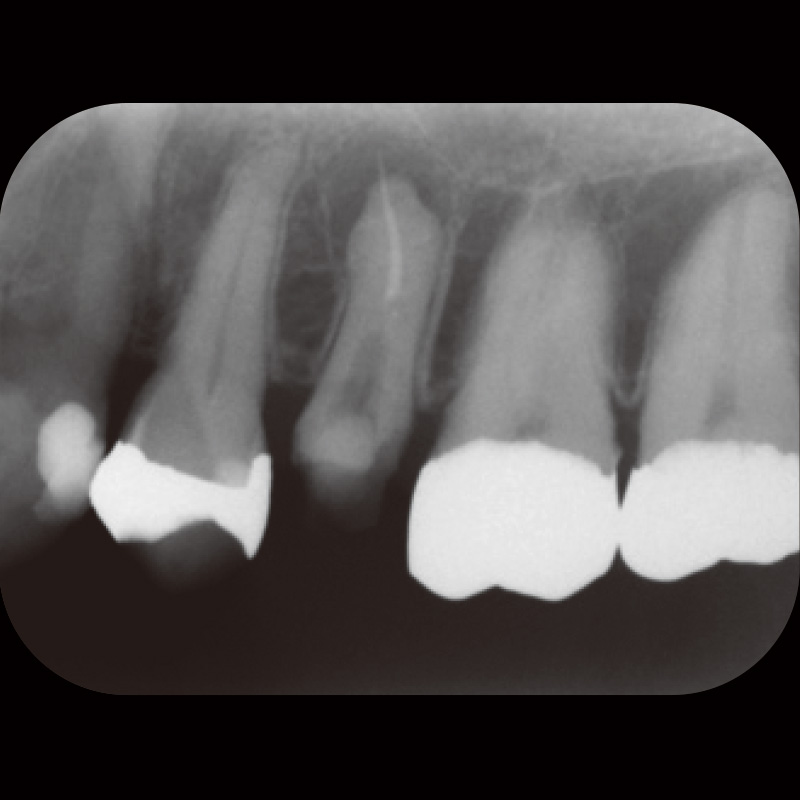

患者は35歳男性で主訴は咬合痛であった。自発痛(-)咬合痛(+)・打診痛(+)・根尖部腫脹(中等度)根尖圧痛(軽度)であり、デンタル及びCBCTでは根尖部透過像・著明な外部吸収及び根尖孔破壊・根管充填材・太いポストコア及び根管壁の菲薄化を認めた(症例1-1, 1-2)。

症例1-1 初診時デンタルX線画像![[写真] 初診時CBCT画像](/academic/dentalmagazine/wp-content/uploads/sites/2/2025/11/195-6_photo02.jpg)